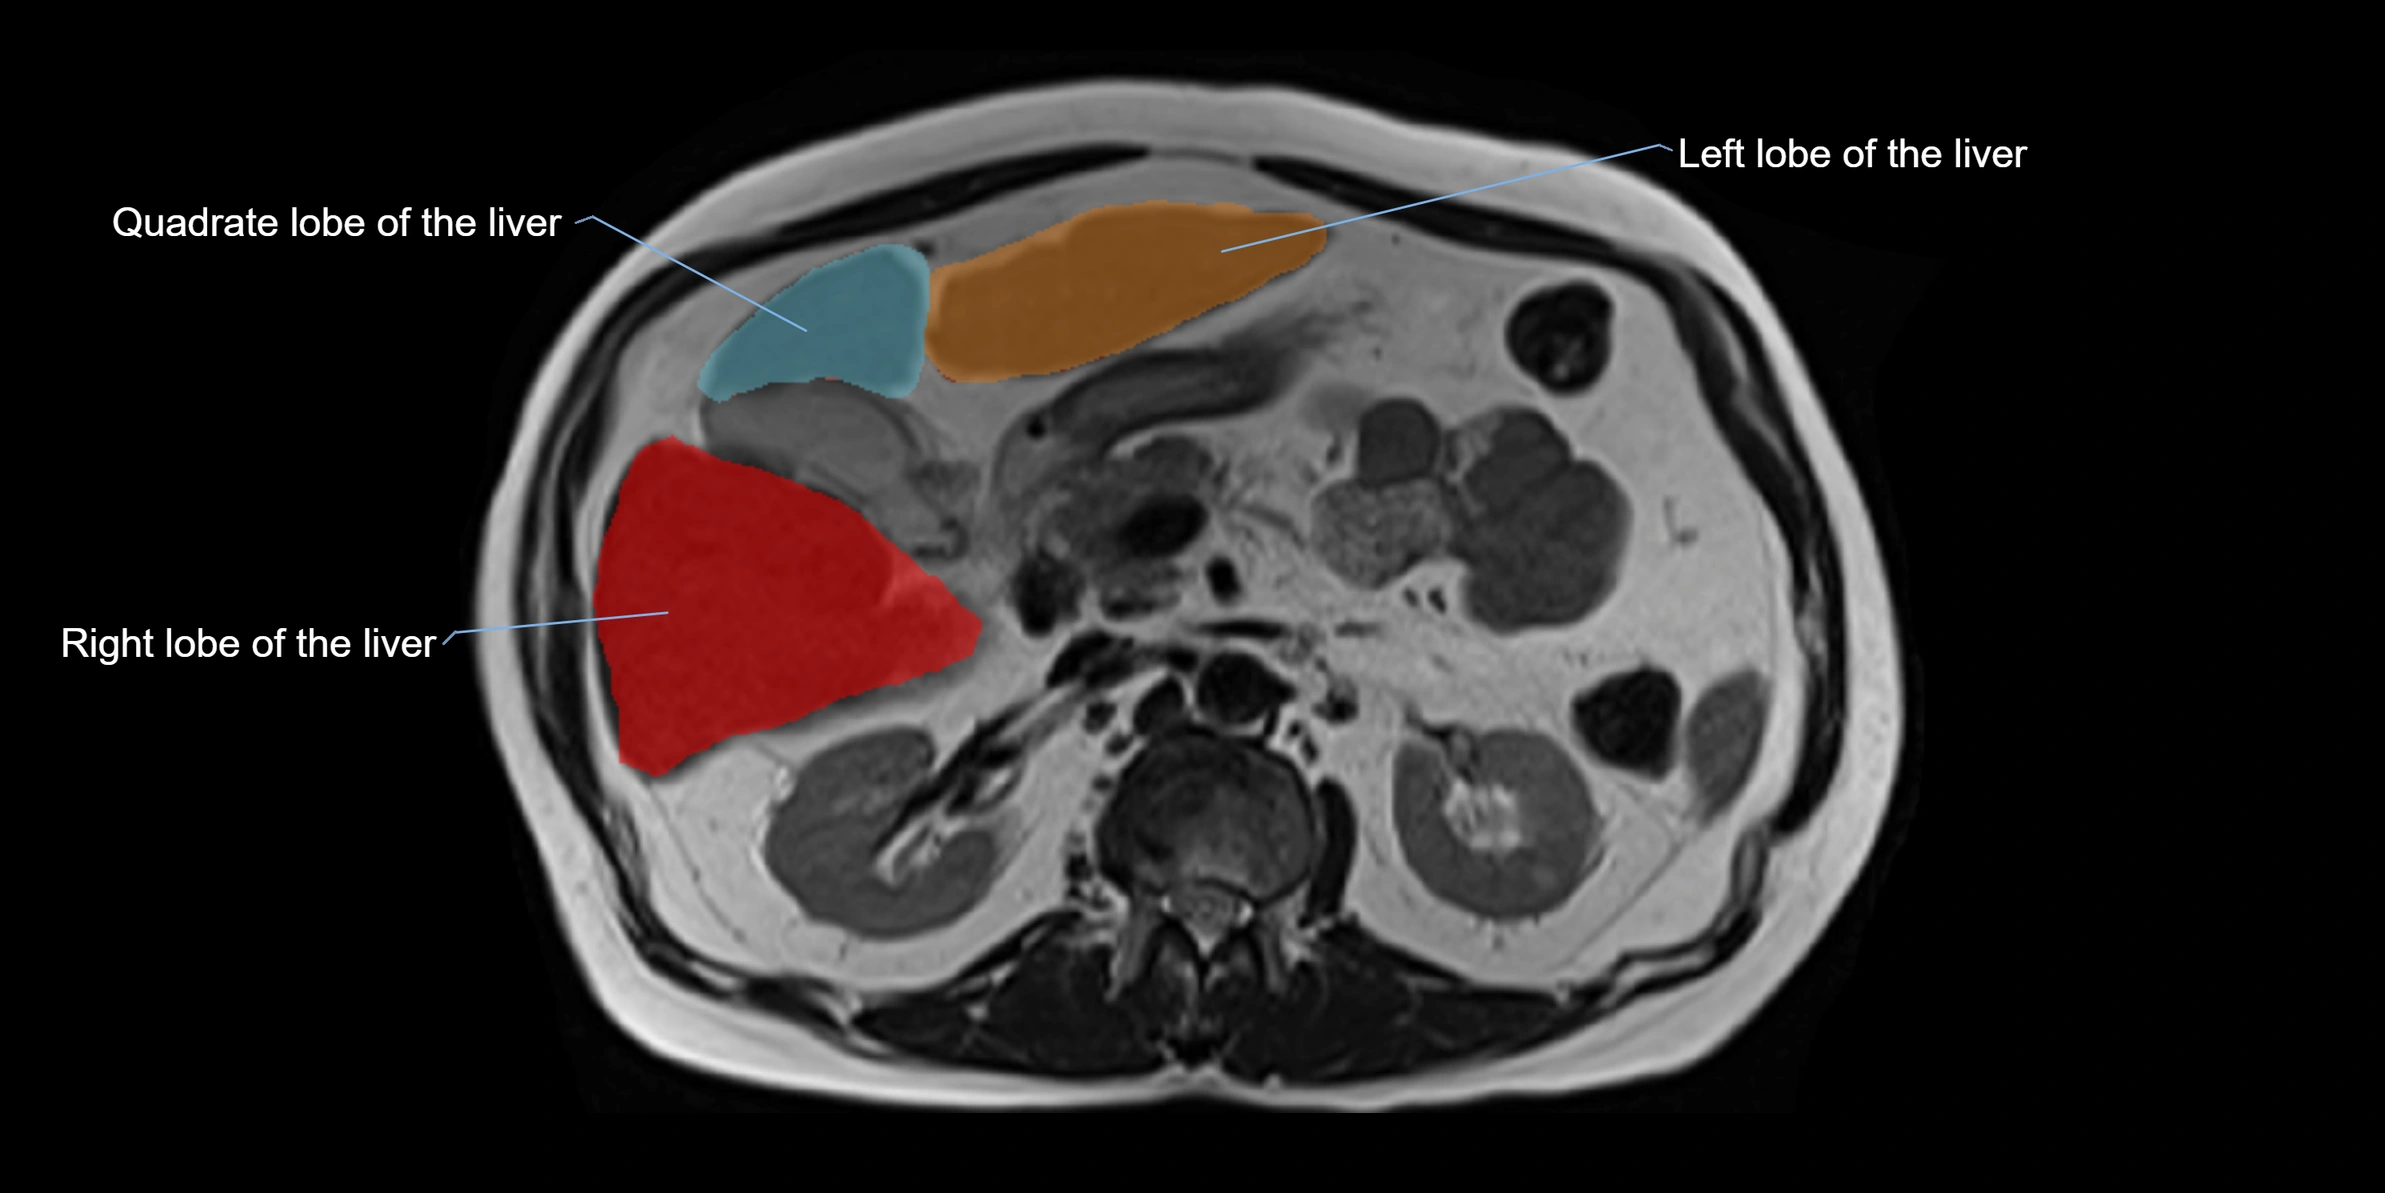

MRI image

image